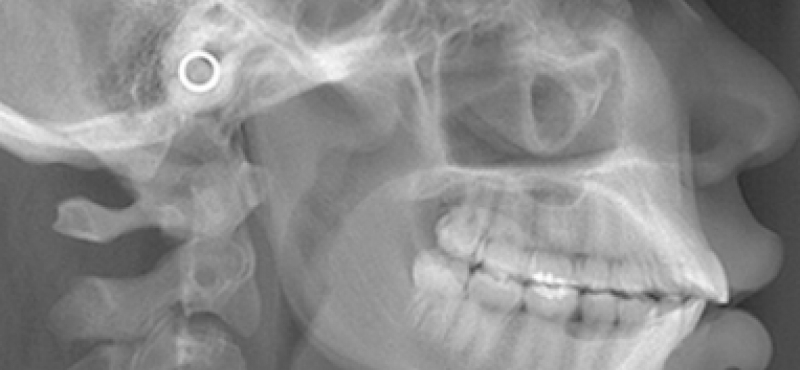

Telerradiografia Lateral Voltar

Este procedimento é empregado principalmente na ortodontia e cirurgia maxilofacial.Sobre esta incidência são realizadas análises cefalométricas onde avalia-se o padrão dento-esquelético-facial e o crescimento do crânio e da face.